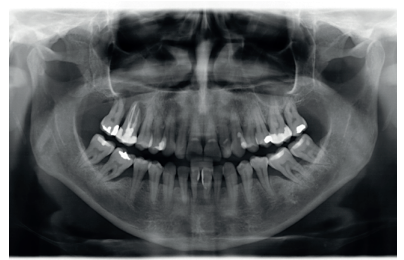

This was the case of a 58-year-old female patient who attended the dentist practice to assess the 16th and 17th molars for pain and mobility. On clinical examination, mobility of both was observed with suppuration at the level of the sulcus. Radiography confirmed our diagnosis of considerable bone loss and sinus perforation at the apex of both molars (Figure 2).

After two months, the dental cone-beam showed the perforation had closed completely but the residual bone volume provided 2 mm of bone height only, which was insufficient to insert the implants (Figures 3 and 4).